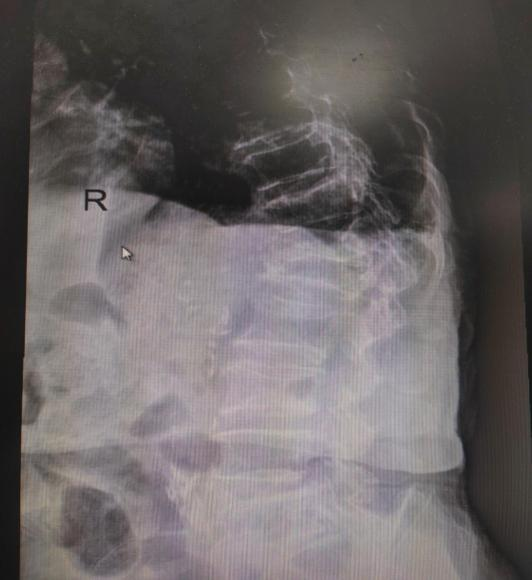

近日,近100歲高壽的潘奶奶,在家上廁所時(shí)不慎摔倒,導緻左股骨頸骨折(頭下型),其家屬急忙將(jiāng)潘奶奶送至惠州六院急診科。經(jīng)急診醫生初步評估後(hòu)轉送至惠州六院關節外科、運動醫學(xué)科病區,經(jīng)過(guò)術前檢查發(fā)現,潘奶奶左股骨頸骨折,又有重度骨質疏松症、雙側髋關節退行性變等20項病症。患者高齡,基礎疾病多,手術風險高。

潘奶奶家屬決定手術後(hòu),關節外科、運動醫學(xué)科團隊考慮到潘奶奶高齡,基礎疾病多,術前快速完成(chéng)腎内科、麻醉科等相關科室會(huì)診及基礎病處理,手術團隊對(duì)術中、術後(hòu)可能(néng)出現的各種(zhǒng)情況進(jìn)行積極讨論,制定詳細的手術方案。